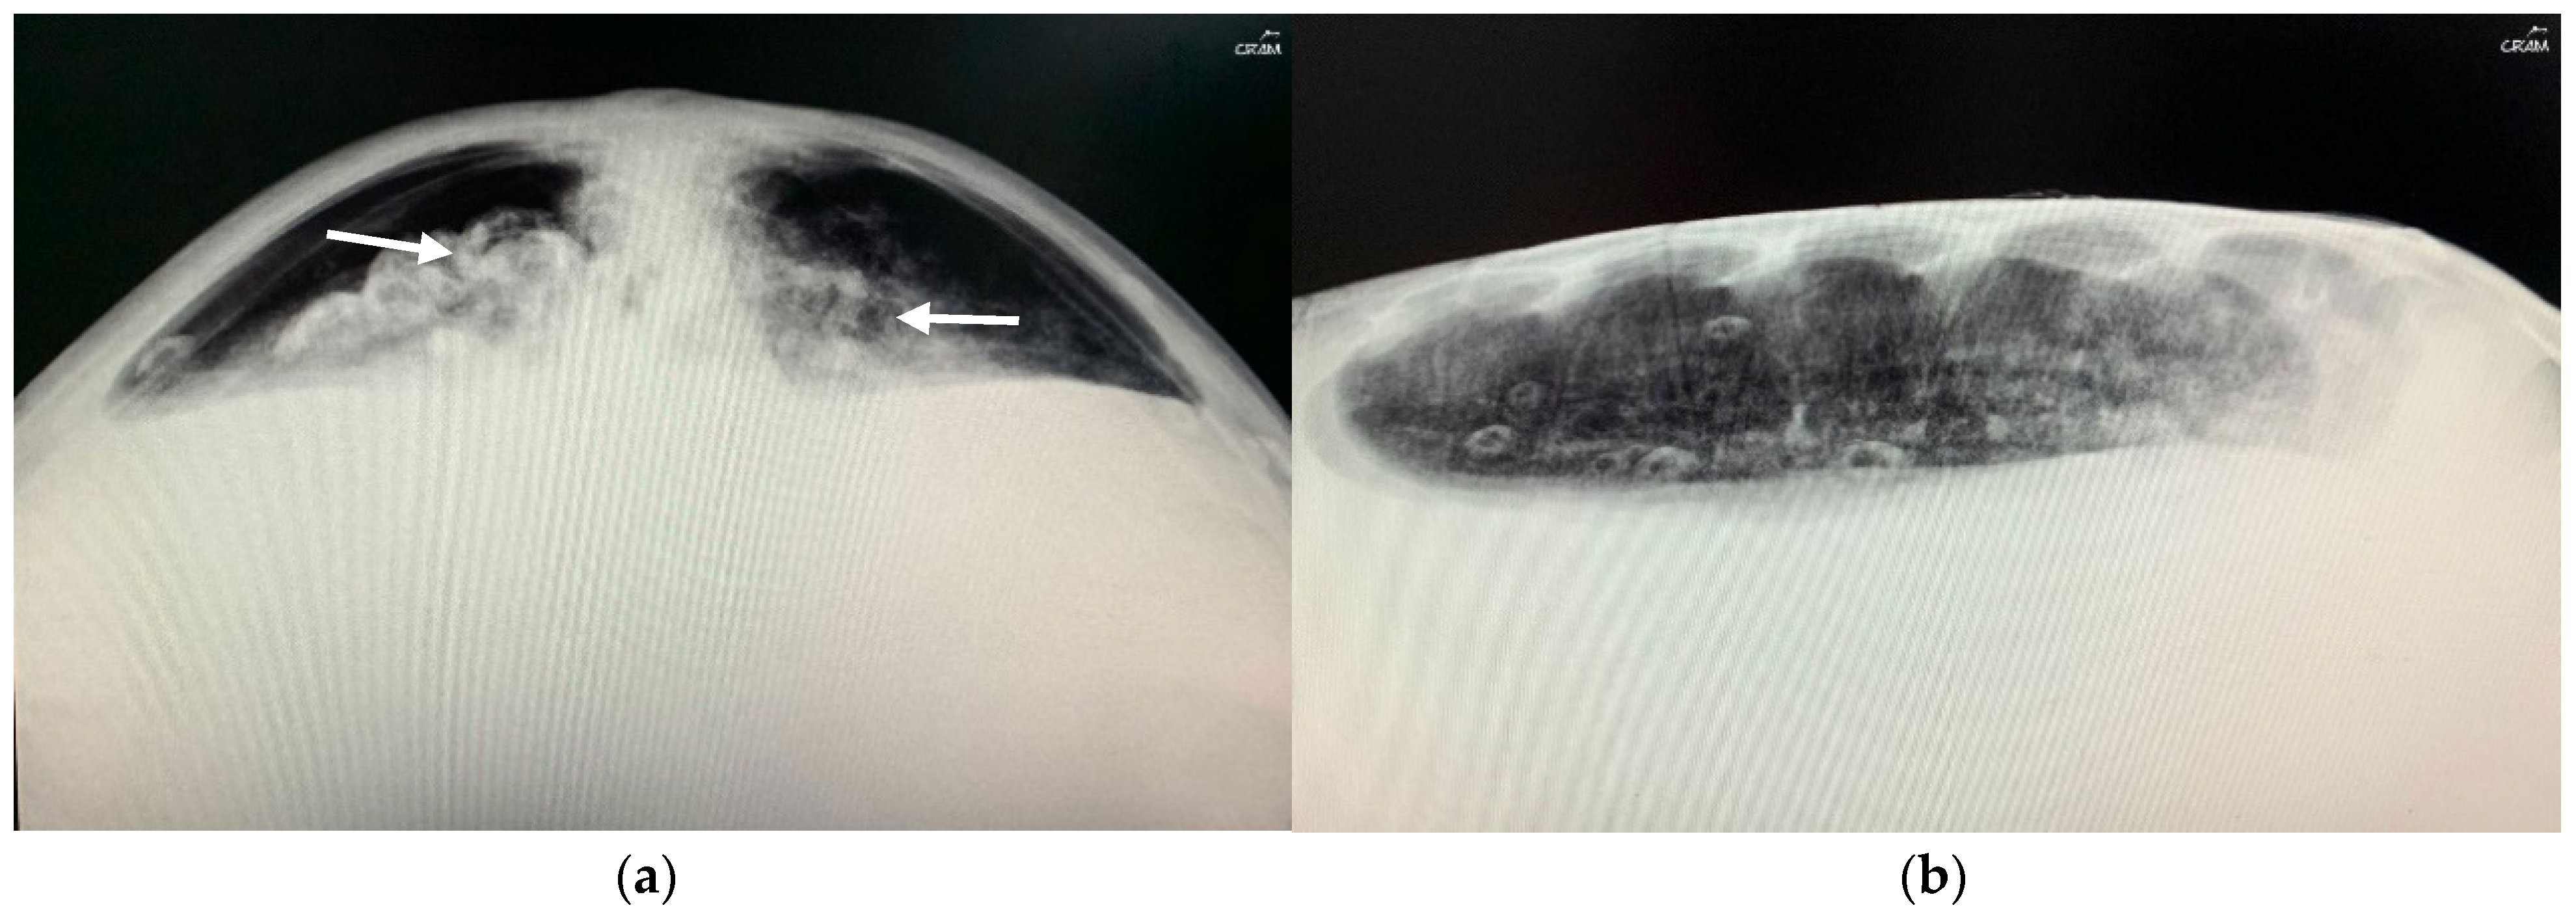

In December 2020, CC20/051 suffered a bycatch incident by a trawler ship. At the rescue center, it was diagnosed with pneumonia by radiography (Figure 3) and started treatment with ceftazidime 22 mg kg−1, SC q 72 h for 15 days. In January 2021, the turtle was released.

Figure 3. Radiographic examinations in cranio-caudal (a) and lateral (b) projections of the lungs. The images show an opacification of the whole parenchyma following bacterial pneumonia. The arrows show a densification of the peribronchial lung parenchyma.